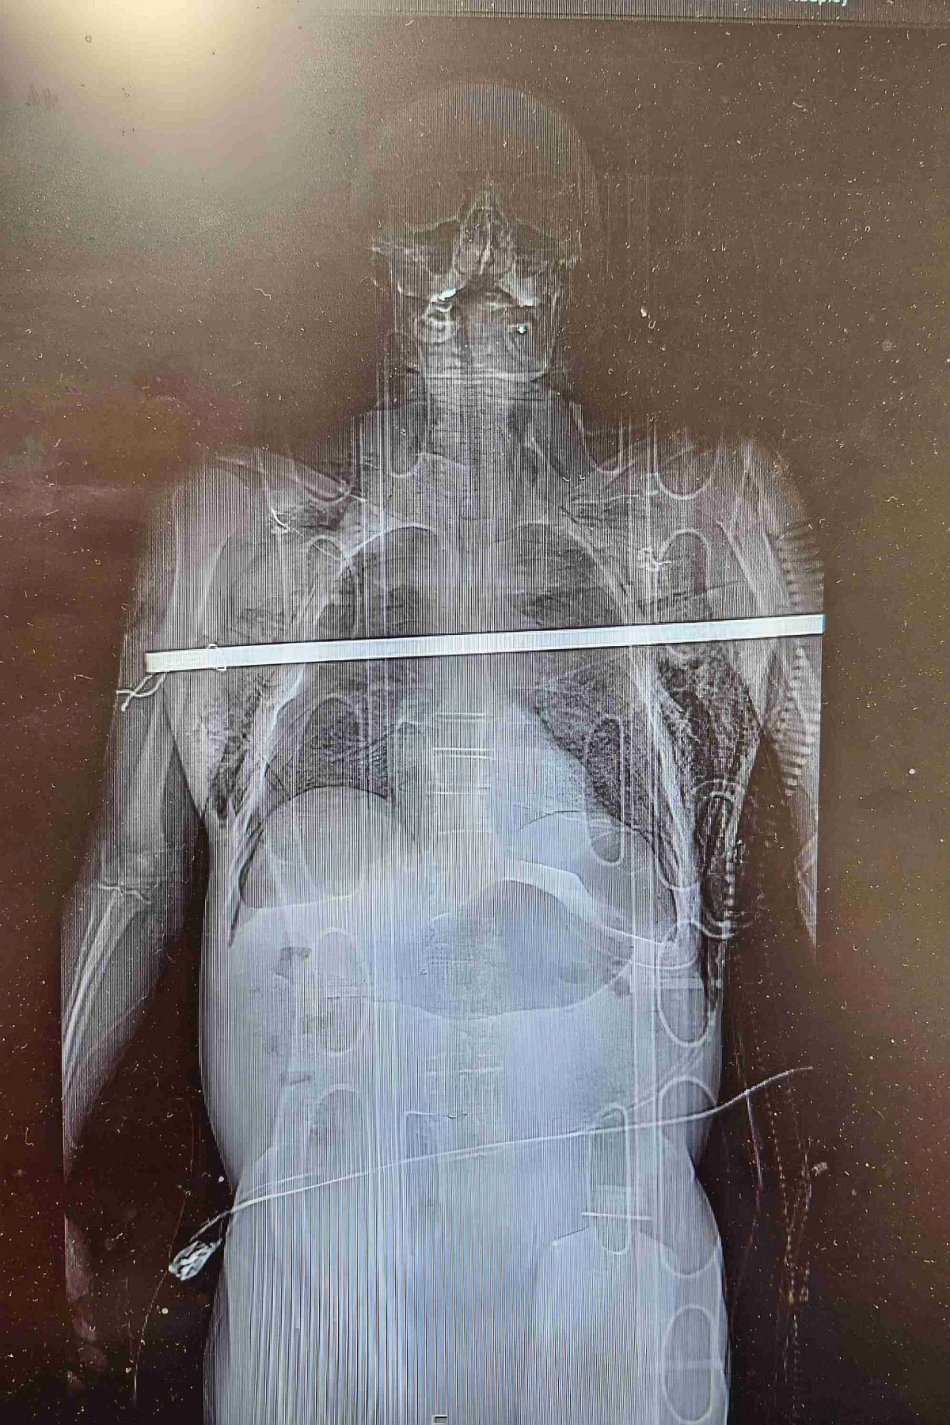

Galéria k článku Radovan sa takmer ZABIL pri oberaní čerešní: Spadol a tyč mu PREPICHLA obe pľúca!

Zdroj: Fakultní nemocnice Olomouc